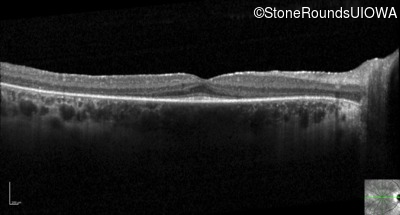

Optical Coherence Tomography - Right -

20/20 -1

Exemplar / OCT Stack

Optical Coherence Tomography - Left -

20/20 -2